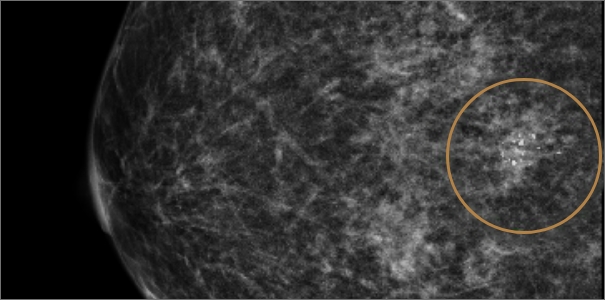

미세석회화

미세석회화란 몸 안에 쌓인 칼슘 성분의 석회질을 뜻합니다.

유방촬영 시 하얀 점으로 보이며 노화, 유선 내 분비물 침착, 염증 등으로 생길 수 있습니다.

대부분의 경우 양성 석회화로 인체에 무해하지만, 유방암으로 인해 생기는 악성 석회화가 의심될 시

조기 발견과 치료를 위해 반드시 조직검사를 통한 악성 여부 확인이 필요합니다.

악성이 의심되는 미세석회화

조직검사로 암의 여부 판별

유방암으로 인해 발생한

악성 미세석회화로 의심되는 경우

맘모톰을 이용해 조직을 추출한 후

조직검사를 시행해 암의 여부를 판별합니다.